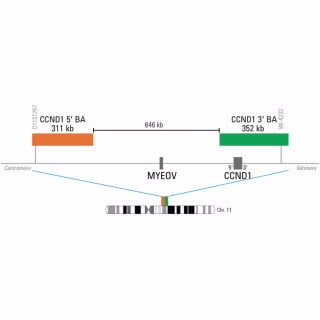

CCND1 IQFISH Break-Apart Probe

Break apart probes consist of two child probes (3’ and 5’ probes), designed to hybridize on opposite sides of the translocation break point for a given gene, each labeled in a different color (Cy3 and FITC). These probes generate signals in normal cells that are closely matched in size and co-localized (2 fusion signals). Following a translocation, the signals are broken apart and no longer co-localize (for example: 1 orange-red, 1 green, 1 fusion).

Child Probe 5' RD, Chr11

Start 68407510, Stop 68718885

Child Probe 3' GR, Chr11

Start 69365371, Stop 69717561